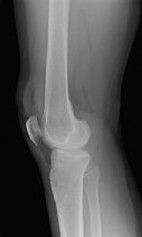

Figures 1 and 2 are the radiographs of a 35-year-old man who is brought into the emergency department after a motor vehicle collision. He is complaining of isolated knee pain. Examination reveals swelling, blood filled blisters, popliteal ecchymosis, joint line pain, and limited knee joint motion. His pulses and sensation are normal.

**CLINICAL SITUATION**